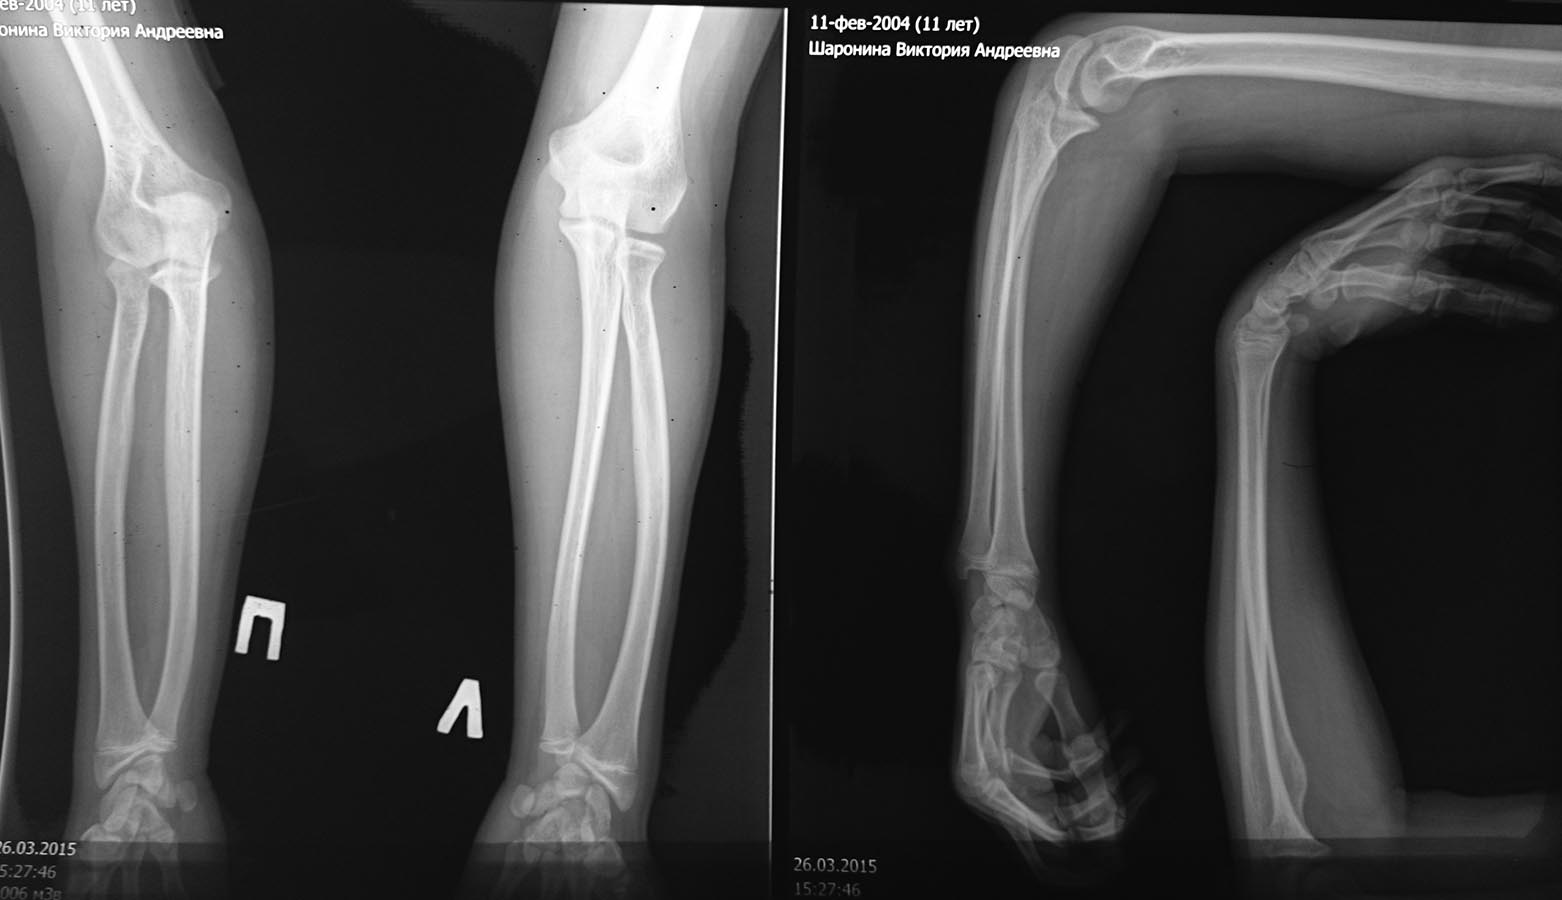

[Ortho] Застарелый вывих головки луча и парез лучевого нерва у подростка.

Для сравнения-рентген здоровой конечности